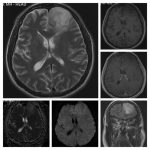

Neurosurgery and neuroradiology always go hand in hand. This little weekly activity is going to enhance the scan reading skills of our audience in an interactive way. Waiting for the answer for a week will keep the curiosity alive and will keep our target audience hooked to the website. It will prove to be a seamless share of knowledge and reading skills.

Dr. Saqib Kamran Bakhshi started the PANS Weekly Image Challenge in 2022, and his creativity and efforts made it a popular activity; engaging trainees and consultants in Pakistan and abroad.